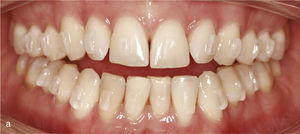

Por medio de la intrusión y de la extrusión se puede lograr no sólo una sobremordida horizontal y vertical fisiológica, sino también la nivelación de la altura gingival. En el paciente de la figura 9a existe una gran discrepancia de la línea gingival entre los dientes 13 y 23, más elevados, los dientes extrudidos 11 y 21 y los dientes conoides 12 y 22. Lo mismo sucede con la línea gingival de los incisivos en relación con los caninos en la mandíbula (fig. 9a). Las situaciones de apiñamiento y giroversión dentarias marcadas en el maxilar y en la mandíbula se pudieron solucionar mediante una expansión y una reducción del esmalte interproximal. La nivelación de los dientes anteriores y, por consiguiente, de la altura gingival se llevó a cabo por medio de la intrusión de los dientes 11, 21 y 32 a 42 y de la extrusión de los dientes 13 y 23. La imagen 9b muestra la nivelación lograda de la línea gingival una vez finalizado el tratamiento con el sistema Invisalign. Después de las medidas ortodóncicas se llevó a cabo un tratamiento conservador en los dientes 12 y 22 con carillas.